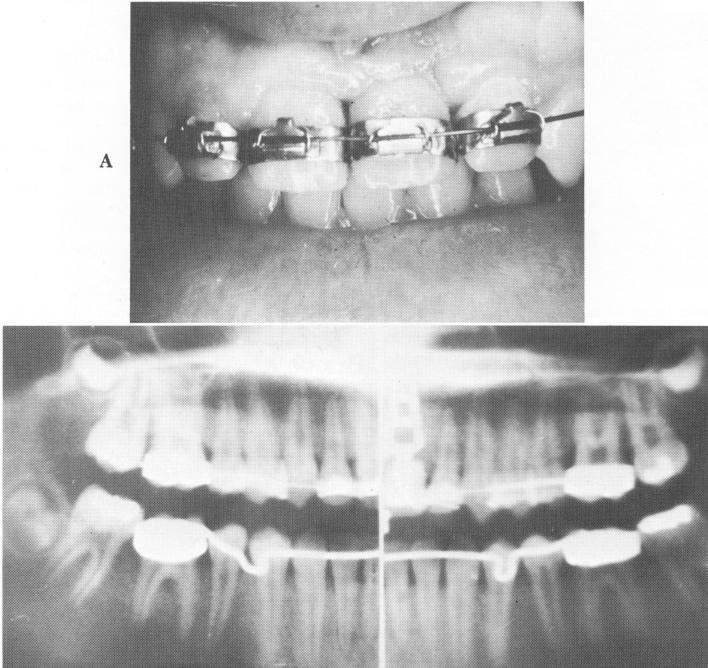

Fig. 15-98. The completed case. A, The tooth was cemented over the implant post and secured to the arch wire. B, The Panorex roentgenogram of the completed case. (From Linkow, L. I.: The endosseous blade implant and its use in orthodontics, Int. J. Orthodont. 8 [4] :149-154, 1969.)

3 Tooth cemented over blade implant post and secured to arch wire